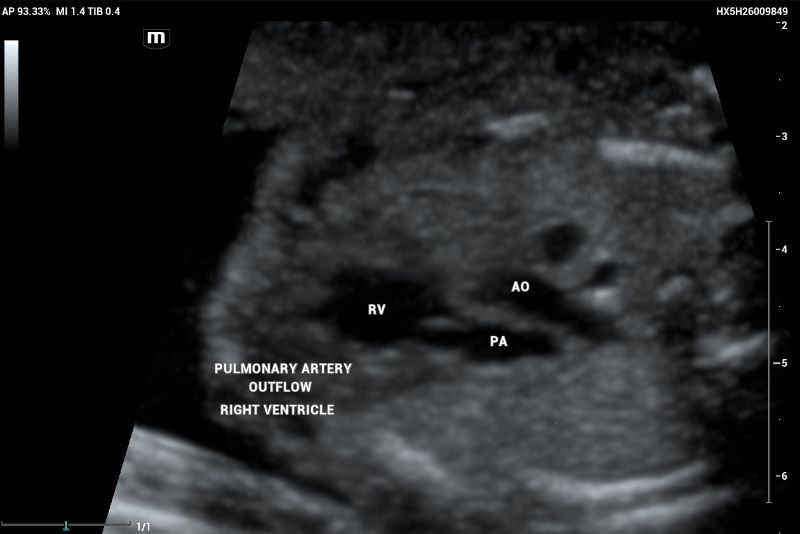

Outflow tract of aortic and pulmonary arteries and functional evaluation (Figure 4-6).

Example of normal echocardiography performed on Mindray Resona I9 system. Artery – ventricle concordance outflow tract showing pulmonary artery (PA) emerging of the right ventricle (RV)

Figure 4. Example of normal echocardiography performed on Mindray Resona I9 system. Artery – ventricle concordance outflow tract showing pulmonary artery (PA) emerging of the right ventricle (RV)